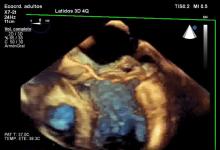

This the case of a 55-year-old male with no record of previous disease or cardiovascular risk factors. At the time of surgery the patient was asymptomatic. TEE showed severe mitral regurgitation (MR) secondary to prolapse of the posterior mitral leaflet. The prolapse of the P2 segment with broken chordae was visible without doppler. A severe MR Jet was visible with doppler.